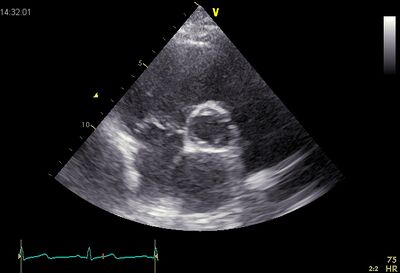

Echocardiographic views

Plax TV02.jpg Psax ao.jpg

Plax by tilted PSax Ao